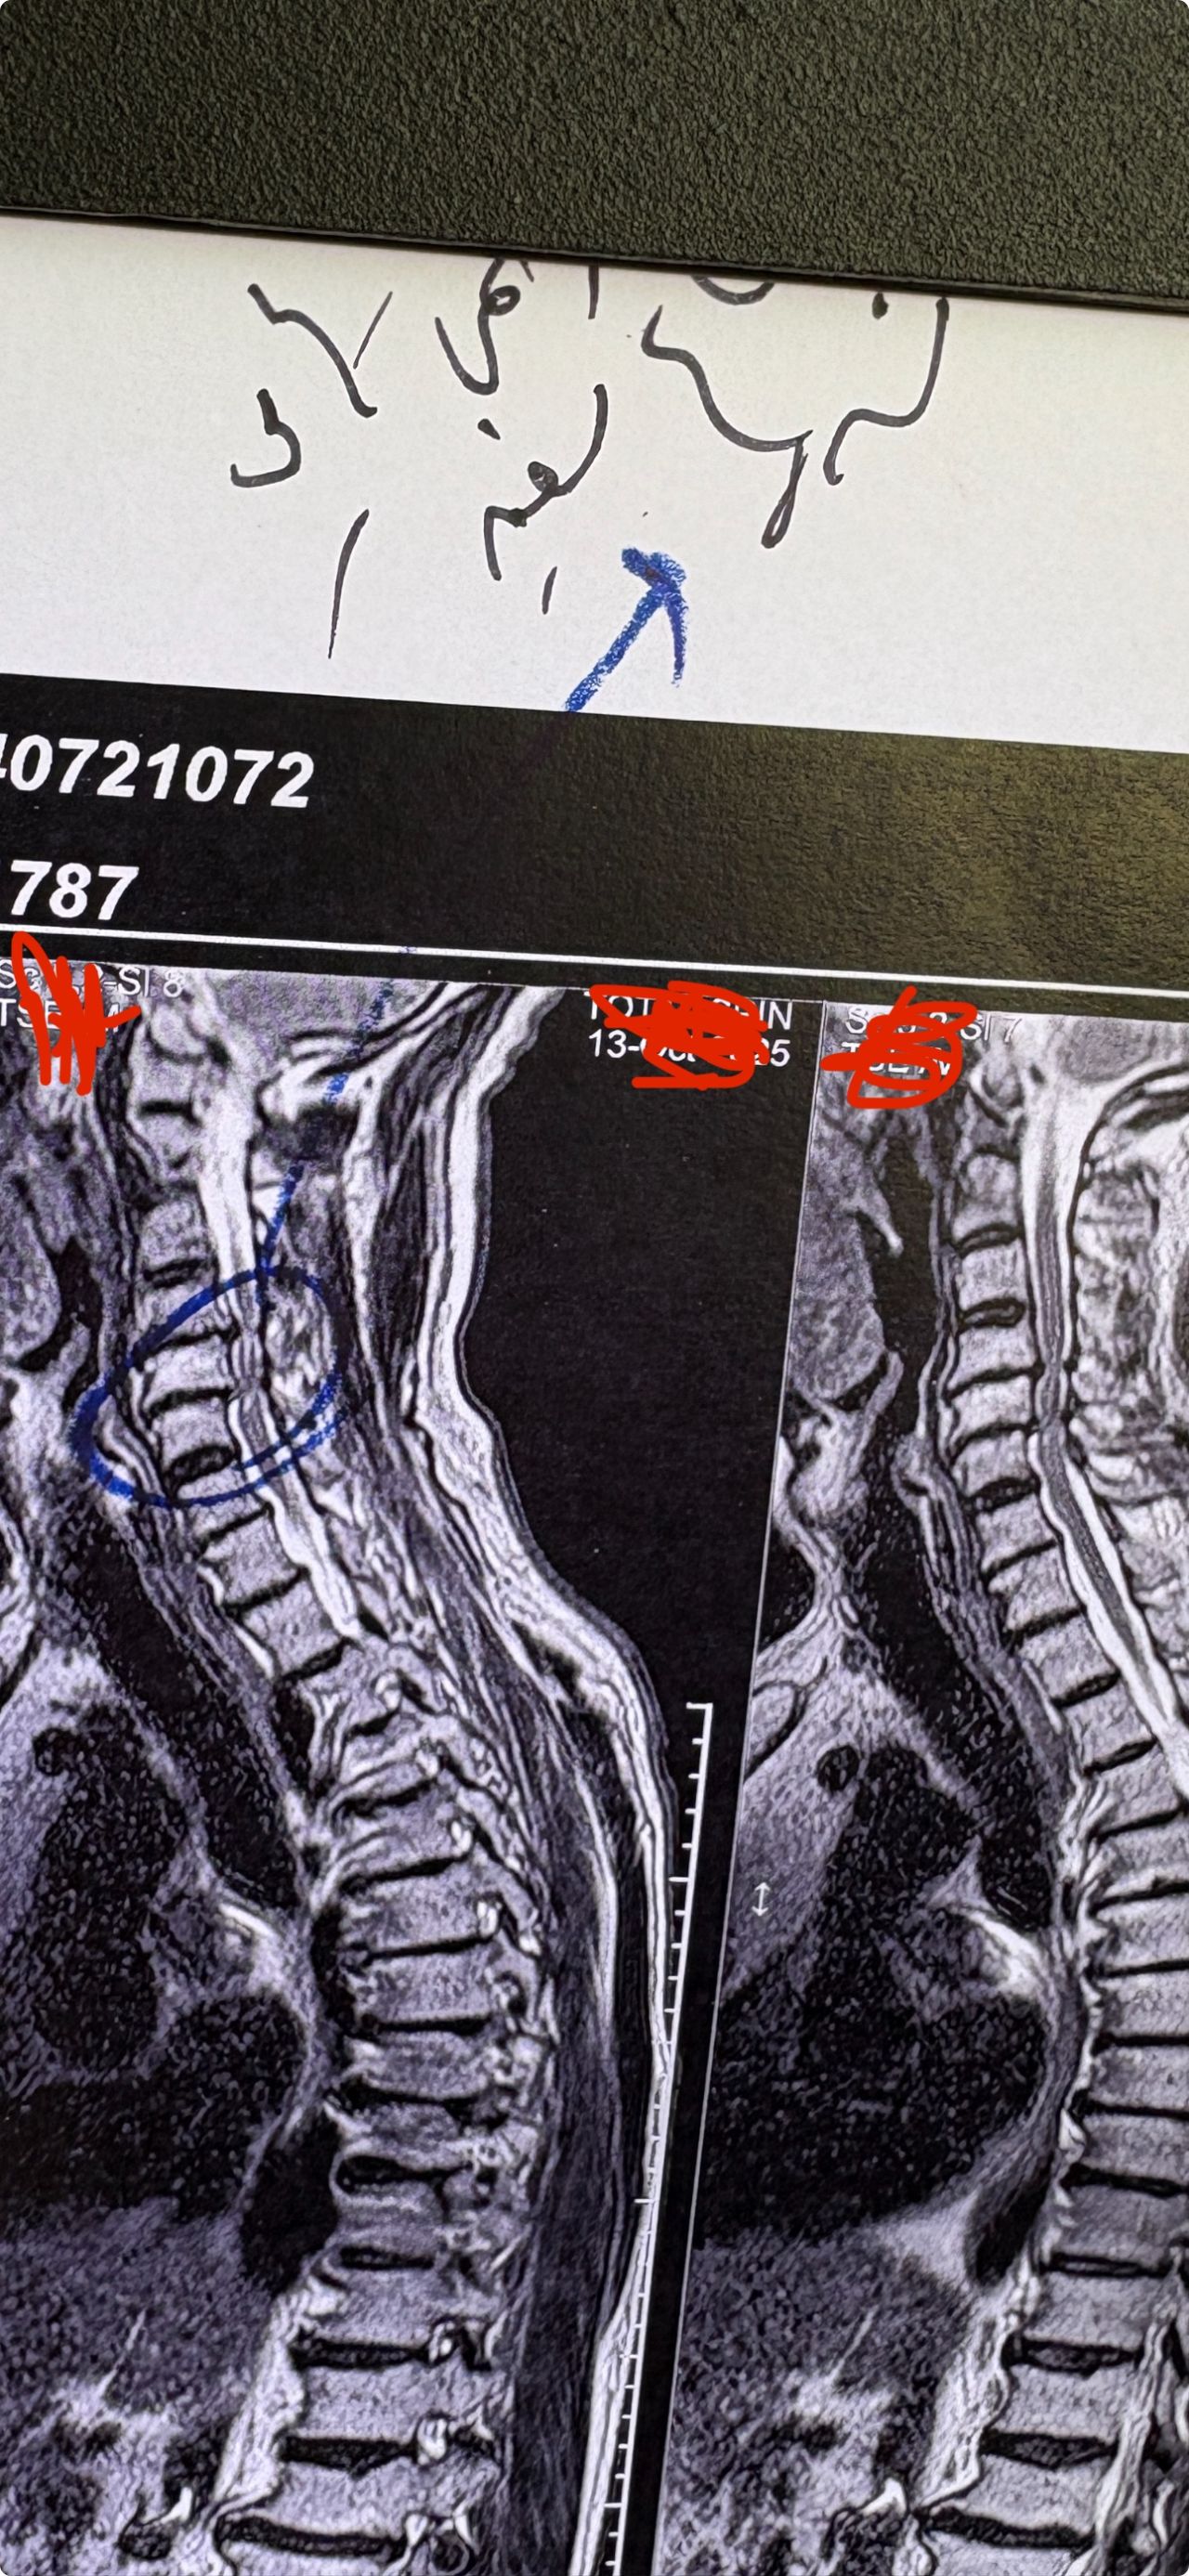

53 yrs old femal presented to my clinic on Jan/2025 with neck pain which was started 40 days ago. In the last 5 days pain was increased without any radicular pain. Had done mri and saw an experienced chiropractor and got 5 sessions of cervical adjustment/SMT which was so helpful in decreasing her pain. I repeated her cervical mri and did EMG/NCV( just had mild c5,c6 radiculopathy). In examination had no UMN signs. I have posted her mri before and after adjustments by another chiropractor.

I didn’t accept her for treatment.

Was cervical SMT a wise decision to treat her cerical disc Extrusion? What could be her complications after adjustment(even though her pain was reduced a lot after those adjustments?)

If you had visited this patient first, what would be your plan of management for her?